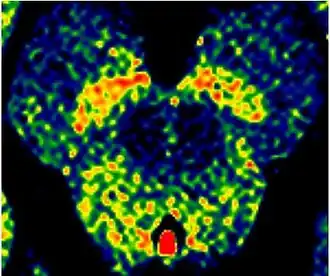

Enhanced Neuromelanin MRI with Color images (RGB) showing Substantia nigra pars compacta

Enhanced Neuromelanin MRI with Color images (RGB) showing Substantia nigra pars compacta -